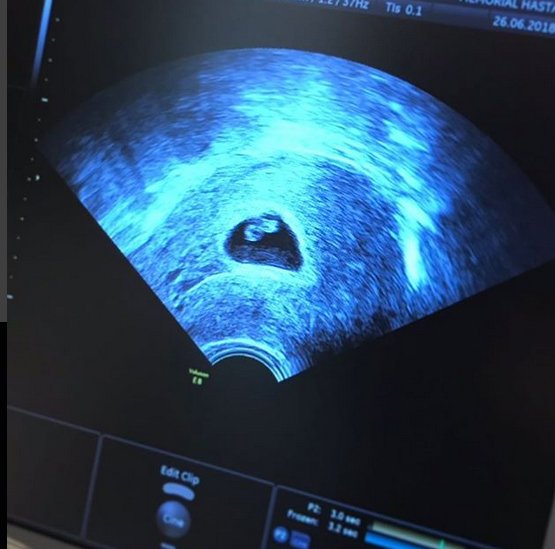

28 Nisan'da iş adamı Ersin Kayalar ile evlenen sosyetik güzel Siren Ertan, tüp bebek tedavisi ile 47 yaşında hamile kalmıştı.

Geride bıraktığımız gün gittikleri doktor kontrolünde bebeğinin kalp atışlarının zayıf olduğunu öğrenen ve takipçilerinden minik yavrusunun sağlığına kavuşması adına duar isteyen Siren Ertan acı haberi yine sosyal medya hesabından duyurdu. Yaşadıklarına benzer duygular yaşayan pek çok kadının kendisine ulaştığını ve ortak acıların ne kadar büyük olduğunu anlayan Ertan, 'Bezelyem' dediği minik bebeğini daha doğmadan kaybetmiş olmanın verdiği acıyla şunları yazdı: